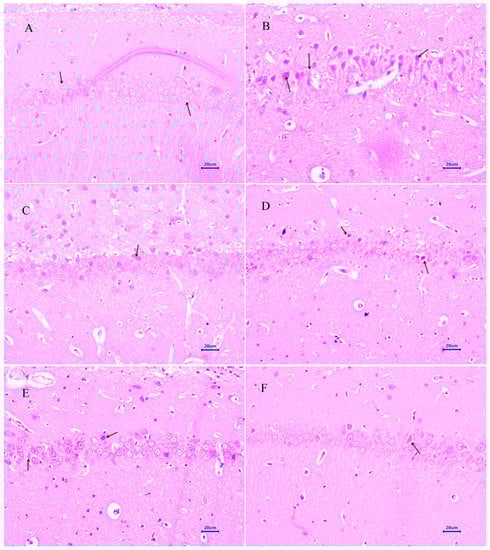

3.4.2. Congo Red Staining

3.5. Immunohistochemistry Assessment (IHC)